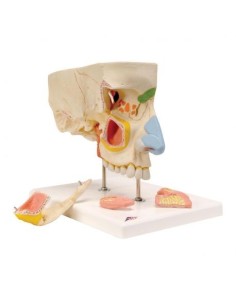

Erler Zimmer, modello anatomico per spiegare la corretta igiene orale D217

Modello di lingua e denti, grandezza naturale, 4 parti Erler Zimmer EZ-D443

Erler Zimmer, modello anatomico di serie di morfologia dentale, ingrandito di 10 volte...

Erler Zimmer, modello anatomico di metà mandibola superiore e inferiore, ingrandita...

Erler Zimmer, modello anatomico di dente cariato, ingrandito di 10 volte D214